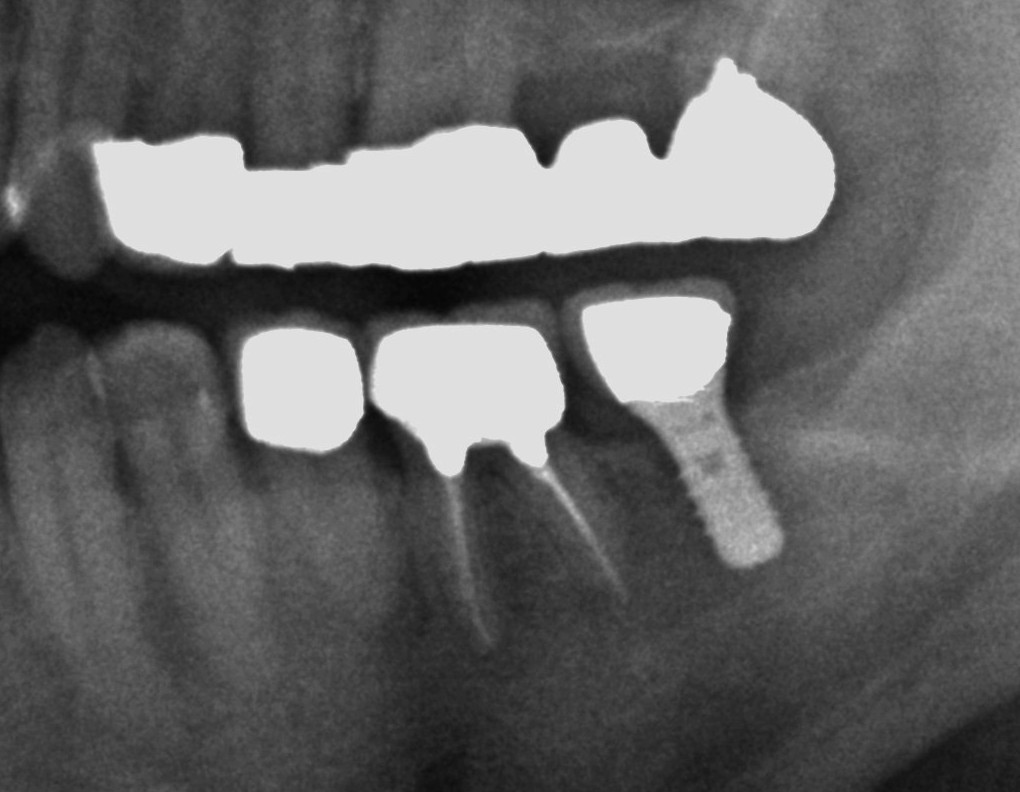

歯科における、歯が無くなった場合に顎骨に埋め込む人工歯根も広い意味でのインプラントの一つであり、正確には歯科インプラント(デンタルインプラント)となります。

しかし一般的にインプラントとは、歯科インプラントの意味で用いられることが多いようです。